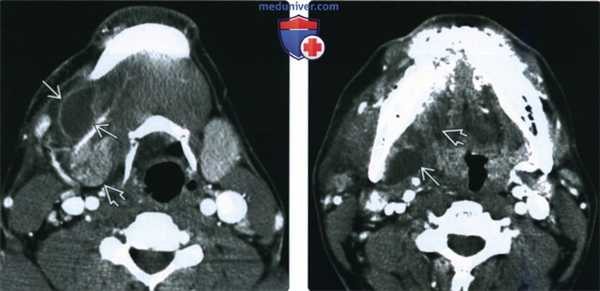

(Слева) КТ с КУ, подросток с жалобами на боль и припухлость в правой поднижнечелюстной области. В правом под нижнечелюстном пространстве, кпереди и латеральнее от железы определяется образование низкой плотности, накапливающее контраст по периферии. Имеются выраженные воспалительные изменения окружающих тканей.

(Справа) КТ с КУ, аксиальная проекция. Задневерхняя часть ранулы В распространяется вдоль заднего края челюстно-подъязычной мышцы. Такая картина характерна для инфицированной погружной ранулы. Обратите внимание на отек дна полости рта справа.

(Слева) На аксиальной КТ с КУ (у молодого взрослого с сильной болью и отеком) в правой ПНЖ (спереди и снаружи) определяется гиподенсное образование, накапливающее контраст В, наряду с распространенными воспалительными изменениями прилежащих тканей.

(Справа) На аксиальной КТ с КУ у этого же пациента визуализируется задний верхний край образования, распространяющегося по направлению к челюстно-подъязычной мышце. Изменения соответствуют вторично (остро) инфицированной HP. Обратите внимание на отек правой половины дна полости рта.